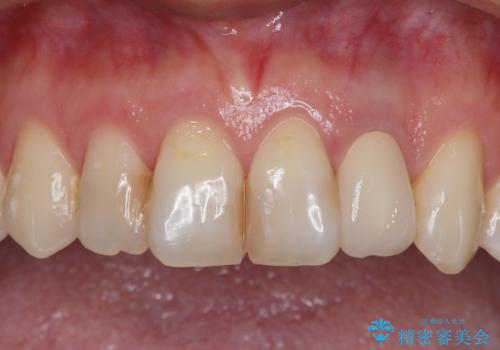

根元がうずく前歯 根管治療とオールセラミック治療

- 前歯に痛みを感じて来院された患者様です。

以前虫歯治療を行った歯が痛み出し、鼻の下を押すと強い痛みを感じていました。

レントゲン写真から、大きくなった根尖病変が認められました。

根管治療を行い、その後オールセラミッククラウンにて補綴治療を行うこととしました。

根管治療後速やかに痛みが消退し、6ヶ月後のレントゲン写真では、根尖部の病変がほぼなくなっていることが分かりました。